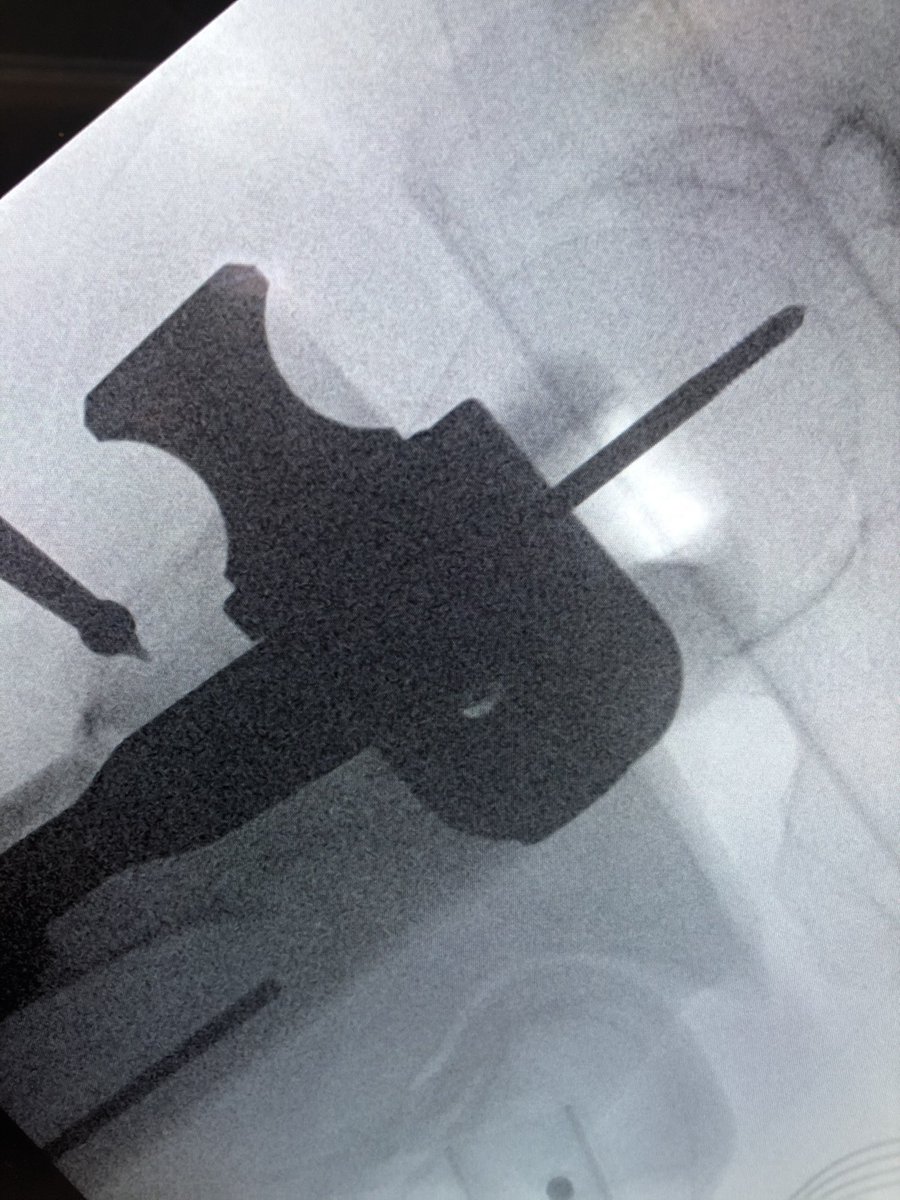

[1/2] Always make sure your wire stays where you put it. The original wire placement for drilling was this, but after drill came out so did the wire, and the screw was placed over the wire without ascertaining that it was back in proper position...

[2/2] This resulted in a completely different (anterior) trajectory of screw placement (left), which then had to be corrected (right). So always check.